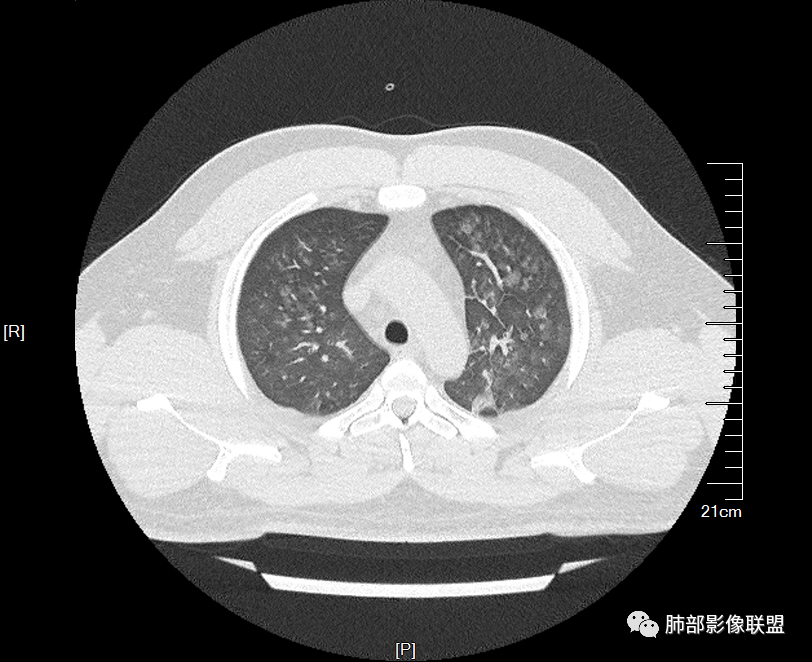

多发GGO结节,边界清,以全小叶、小叶中心为主:

GGO背景

小叶间隔增厚,无明显重力趋势

少量积液,脂肪肝

这里有一点重力趋势

中轴间质稍增厚

细网格也明显

中轴间质增厚,小叶间隔增厚,小叶内间质增厚,部分重力作用,双侧对称,胸水,按理淋巴道回流受阻有

肺水肿类病变有

问题是腺泡结节如何解释?

一般吸入性病变,肺泡腔充填性病变